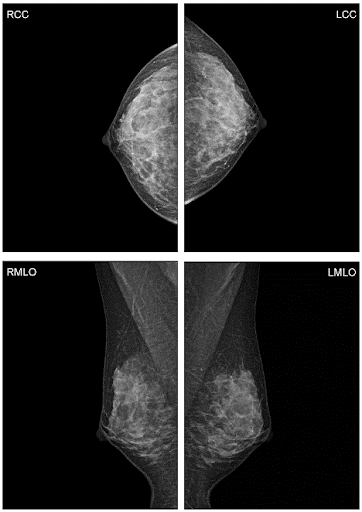

Шаг 2. Виды цифровой маммографии